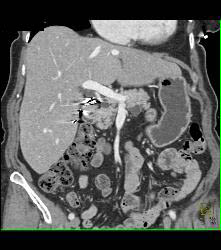

Duodenal Lipoma